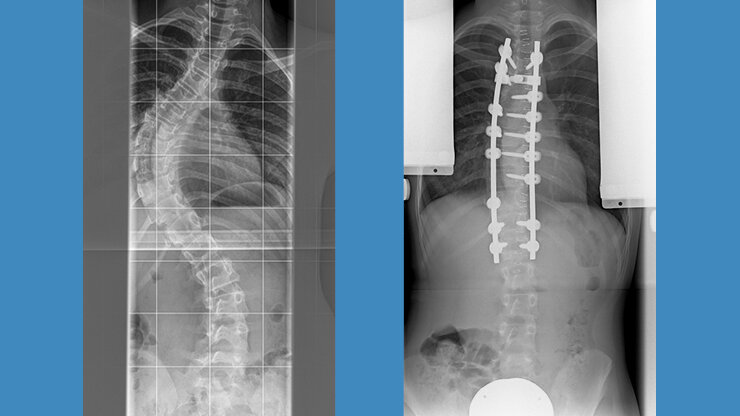

Dorsale Skoliose-Operation

Der Großteil der Skoliosen wird heute von hinten, also dorsal, operiert. Dank moderner Systeme sind ähnlich kurze Operationsstrecken möglich. Patientinnen und Patienten liegen während des Eingriffs auf dem Bauch und die Wirbelsäule wird durch einen mittigen geraden Schnitt freigelegt.

Anschließend werden Schrauben in den Wirbelköpern verankert, an denen die einzelnen Wirbel dann ausgerichtet werden können. Durch neue Techniken mit Schrauben, die auch eine  Drehung (Derotation) der einzelnen Wirbelkörper erlauben, können mittlerweile ähnlich gute Ergebnisse, wie mit der Skoliose-OP von vorn, erzielt werden. Desweitern können von hinten zusätzlich noch die Wirbelgelenke gelöst werden, um die Wirbelsäule flexibler zu machen. Der Rippenbuckel wird durch Osteotomien der Rippen korrigiert und Schmerzkatheter werden entsprechend eingelegt.

Thorakolumbale Krümmung Th 10 bis L3 von dorsal

Thorakale Krümmung Th 3 bis 12 von dorsal